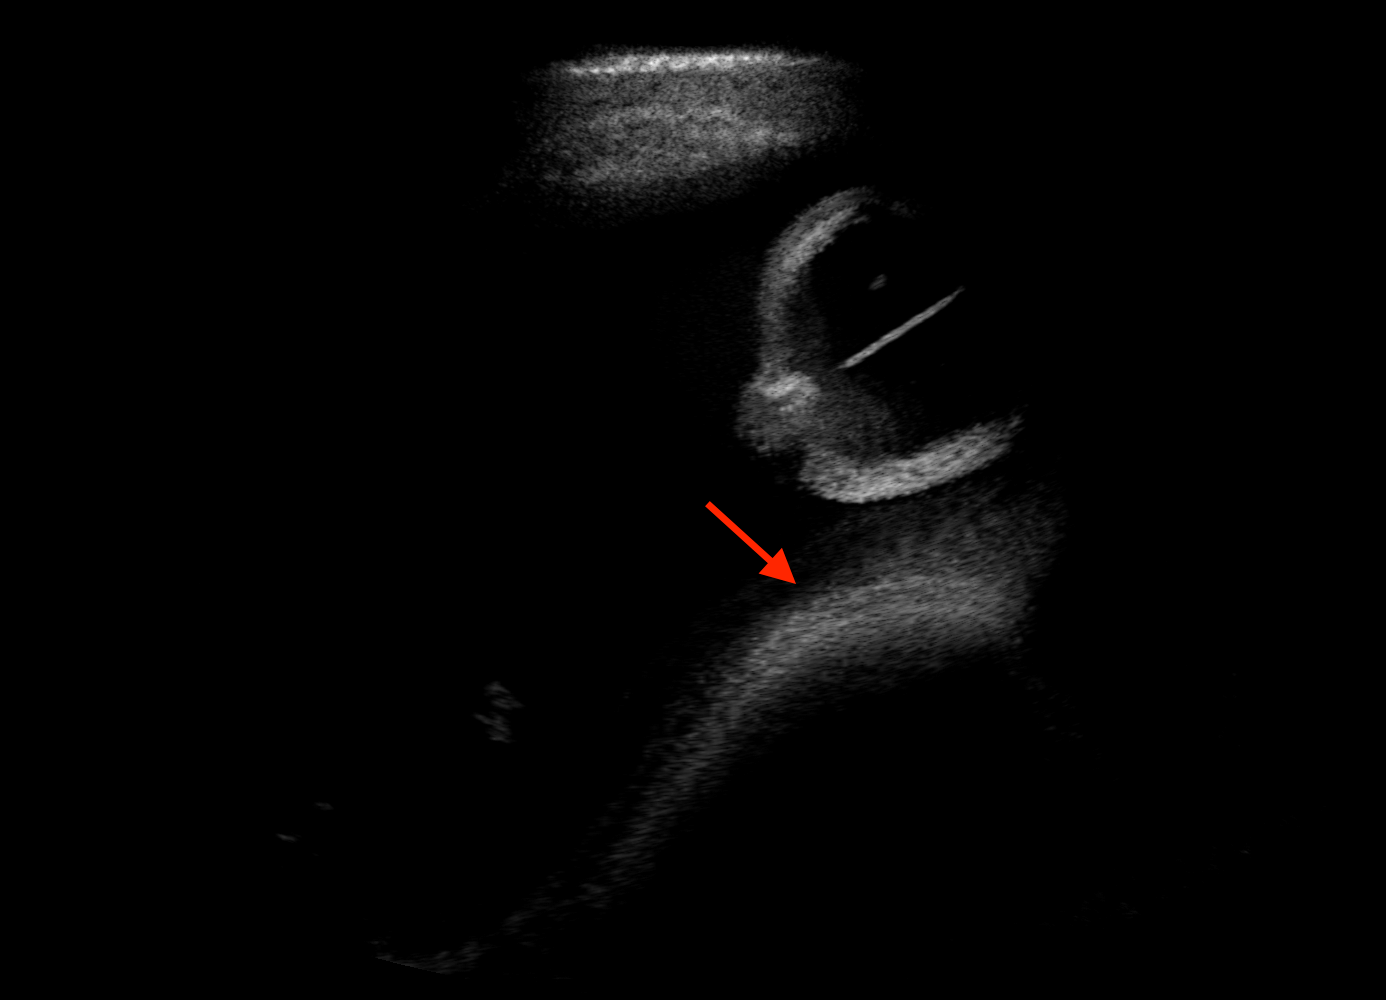

Qualitative evaluation.

Fig. 2 depicts the qualitative results for all the models mentioned above, with arrows pointing at structures relevant to discussion points below. The visual results of the ablated variants of SA2H show substantial quality degradation compared to the full SA2H model, demonstrating the importance of each proposed architectural contribution. Given only segmentation map in the network input, SA2H-att fails to generate acoustic shadows, e.g. those cast by the ribs. Detailed structures such as the cervical vertebrae are blurred out in the SA2H-concat results, which also contain hallucinated structures mainly due to insufficient preservation of input information along the encoding-decoding path. With SA2H-conv, checkerboard artefacts are observed due to the lack of proposed additional stride-1 convolutional layers. SA2H-noise without any explicit noise input is seen to be sub-optimal at generating textural details. The baseline method NSA2H fails to preserve anatomical structures and acoustic shadows in all cases, while the simulated textures also show significant artefacts such as checkerboard patterns. Realism of different simulation aspects may become relevant given different clinical applications and scenarios. For instance, improved structural preservation, e.g. with the hyperechoic bony structures such as the skull and the ribs, of the final model over its ablated variants and NSA2H may prove relevant in fetal head measurements, while the textural improvements facilitating screening fetal organ maturity, e.g. lungs. Compared to the silver-standard model LSA2H with a low-quality rendered image as additional input, SA2H is seen to be on par in structural preservation. Note that shadowing on homogenous regions (e.g. the rib shadowing on the homogenous lung region on the 4th column of Fig. 2) with our proposed method SA2H is represented more faithfully compared to LSA2H, whereas shadows on structurally complex regions (e.g. the skull shadowing around the heart and surrounding tissues on the 3rd column of Fig. 2) are suboptimal with our SA2H. Therefore, one may have to evaluate our method given particular simulation tasks, e.g. its clinical validity for fetal heart exams. However, even with low quality rendered images, LSA2H leads to artificial enhancements of intensities, lack of acoustic shadows, and low-quality textures especially near the probe, for which SA2H yields satisfactory results as illustrated in Fig. 2.

For the interpretation of the local errors, sample spatial p error maps are depicted in Fig. 3 for LSA2H, NSA2H, and SA2H for the middle two examples shown in Fig. 2. Both images generated by NSA2H have a lot of missing structures and accordingly have high error almost all over the map. Artificial skull enhancement with LSA2H is seem to evoke large p error, as shown in the corresponding error map, whereas the bright spots in the error map of SA2H reflect some hallucinated shadows and structure in the brain. All of above mentioned regions of interest are marked by red arrows. In the bottom example, SA2H fails to generate faithful content at the bottom region marked by red circles, which is well indicated by the error map as well.